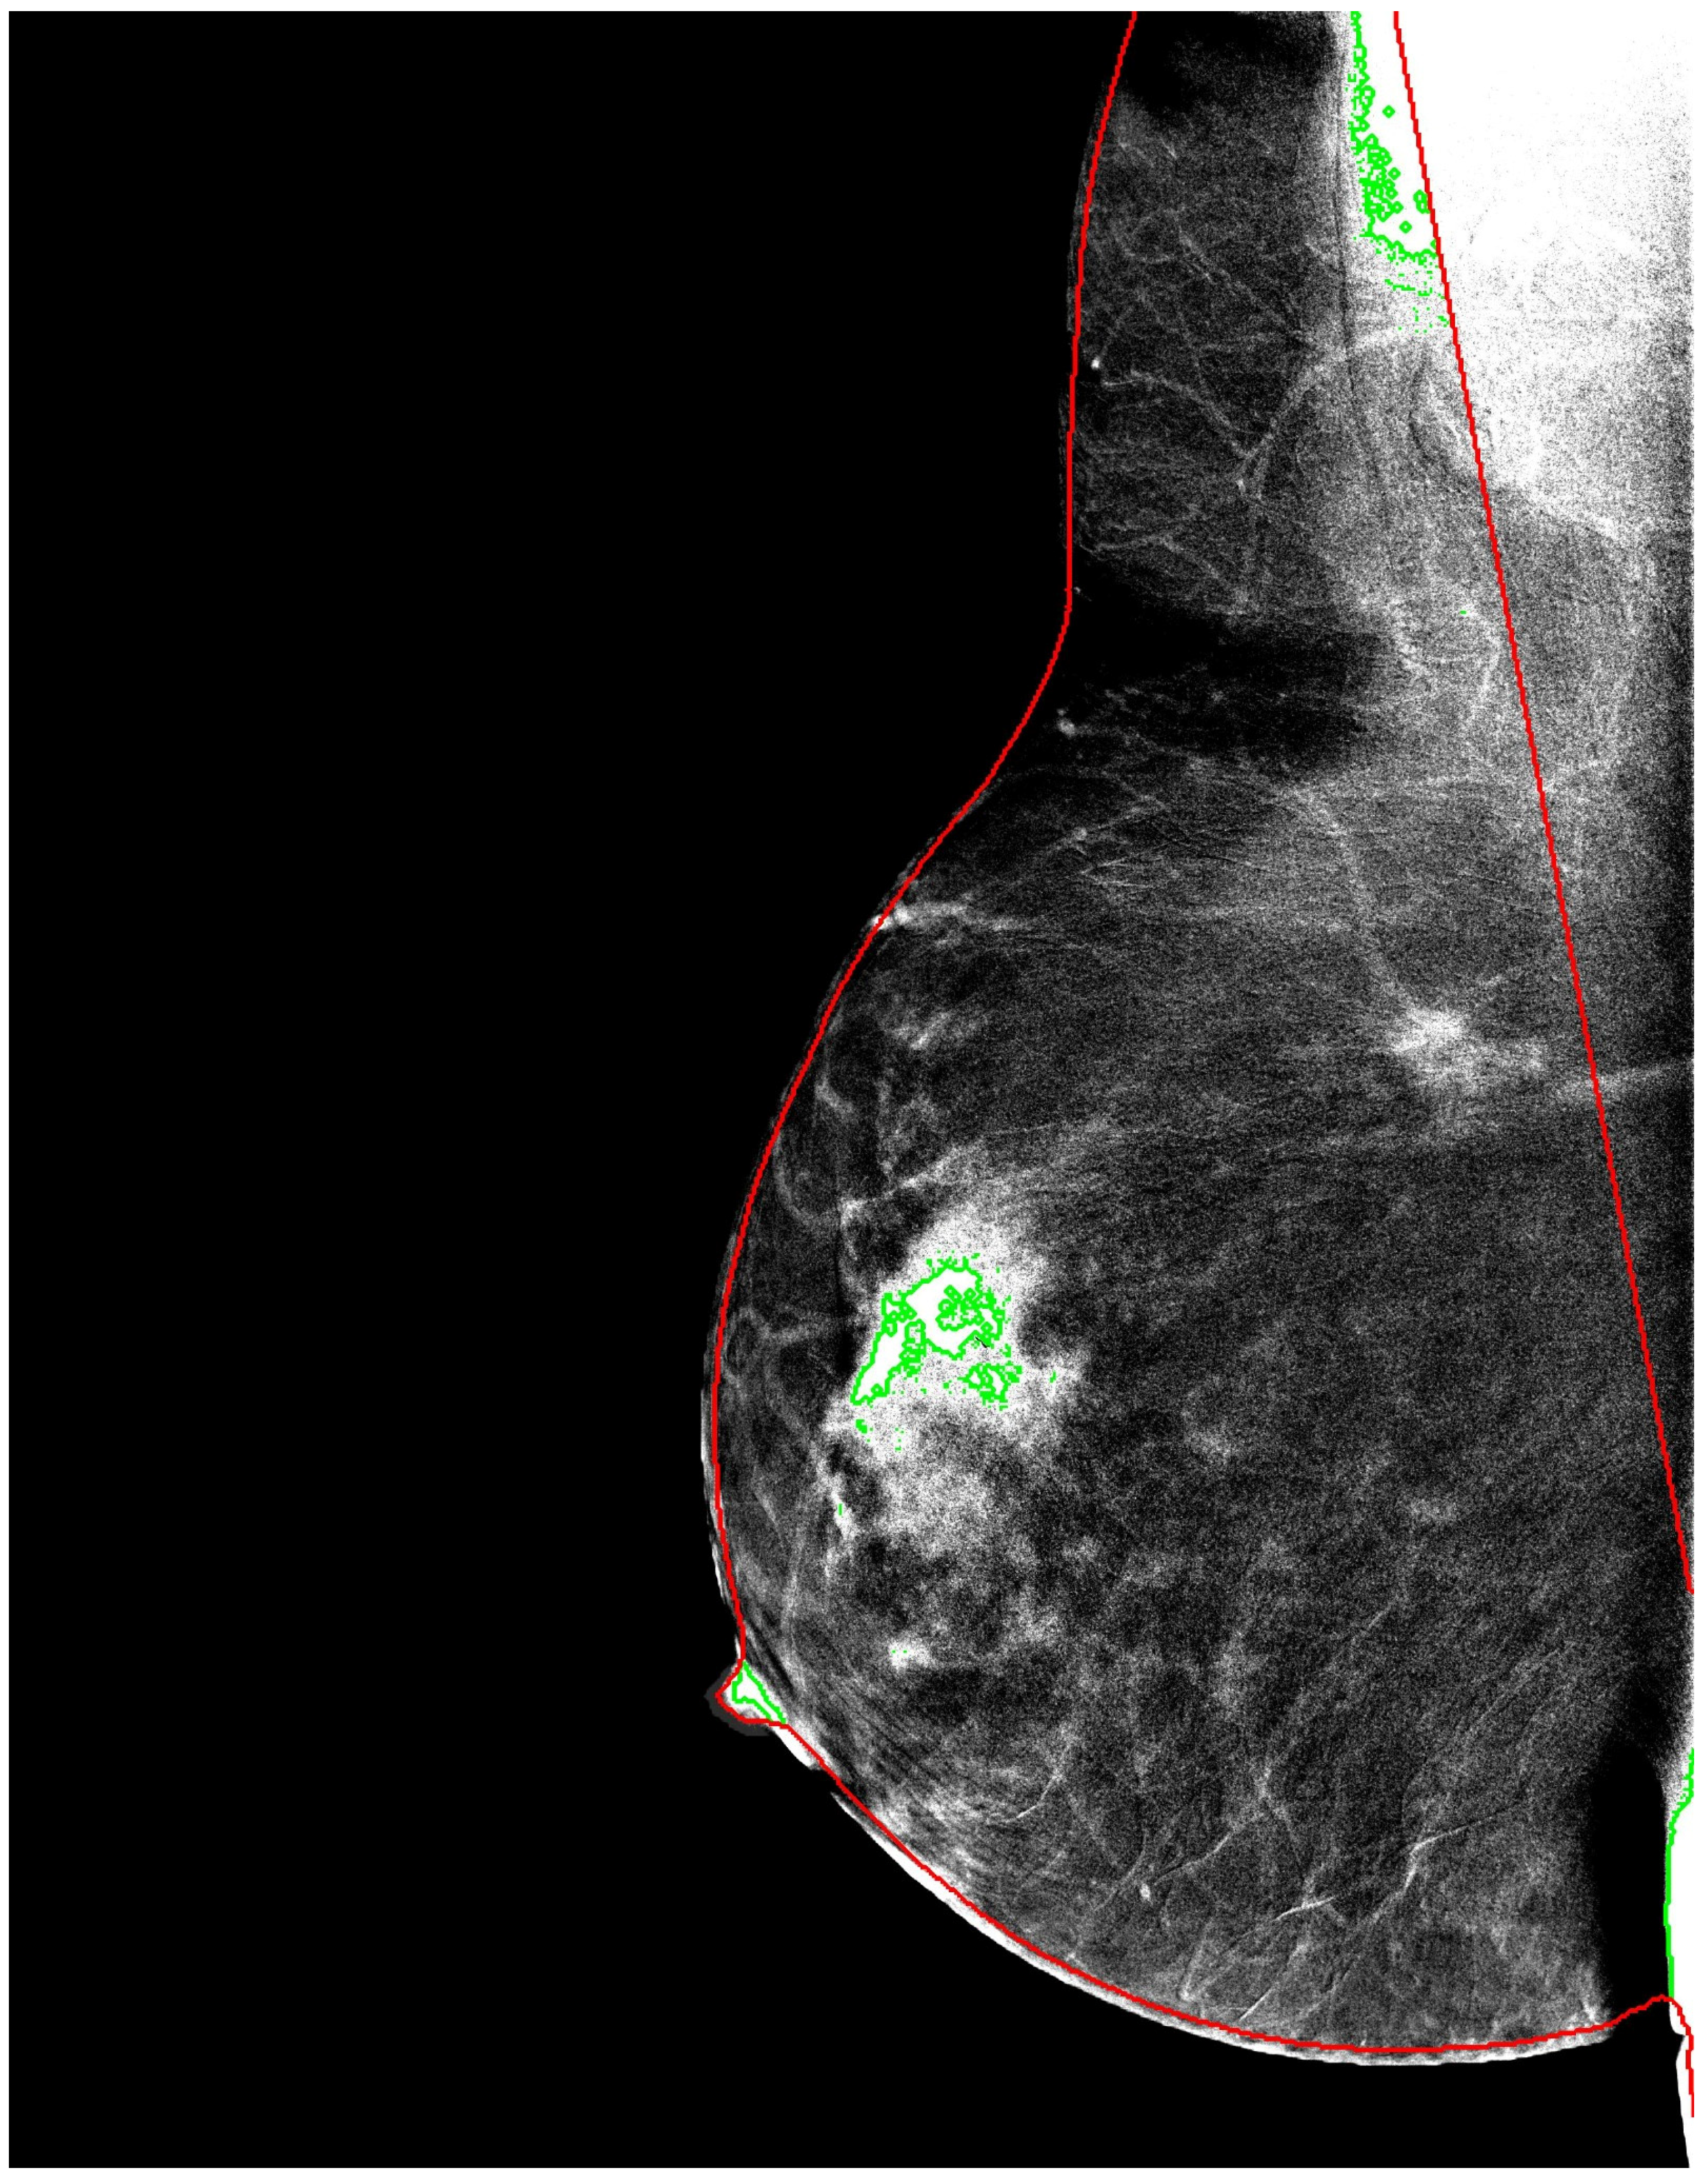

The resulting masks were used to create an alternative input representation, referred to as breast-mask-based images, in which all non-breast pixels were suppressed. This representation explicitly encodes anatomical constraints while discarding background information that is unlikely to contribute to lesion characterization (Figure 1).

Figure 1. Example of breast segmentation using the LIBRA framework. The red contour outlines the breast boundary after background and pectoral muscle removal, while green areas indicate detected lesions within the anatomically constrained breast region.